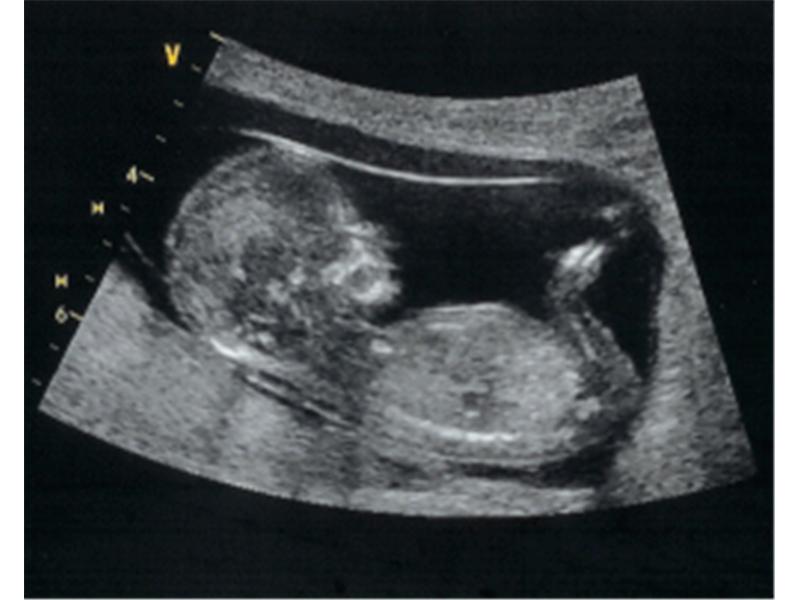

Tak na tohohle výtržníka teď všichni čekáme. Snad se pan doktor nepřehlédl a bude to kluk. Jinak je název téhle galerie tak trochu mimo 😀

Zdroj: archiv redakce